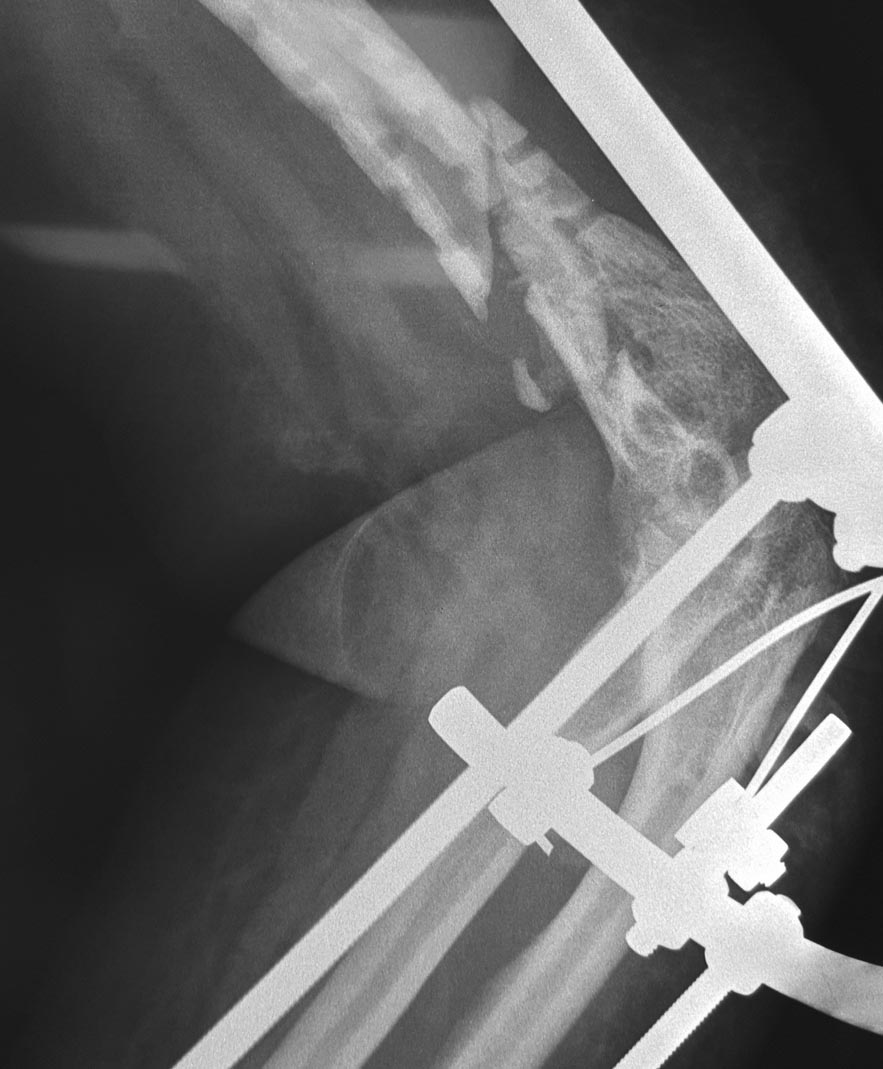

Уважаемые коллеги! Помогите с тактикой дальнейшего лечения пациентки Д 56 лет: февраль 2015 закрытый многооскольчатый перелом левого плеча в дистальной трети,

остеосинтез пластиной с ОК - через 2 недели вырваны дистальные винты, повторный остеосинтез пластиной с угловой стабильностью через 1 месяц вырваны винты, угроза инфицирования гематомы, удаление пластины, спице стержневой АВФ. заживление первичное, последний месяц без свищей и отделяемого.

Наверно, стоило бы начать с улучшения положения отломков в аппарате. Возможно, этот метод в данном случае придется использовать для окончательной фиксации. То есть провести две фронтальных спицы в дистальный отломок, освободить локтевой сустав, одномоментно или дозированно модулями аппарата добиться сопоставления и компрессии отломков.